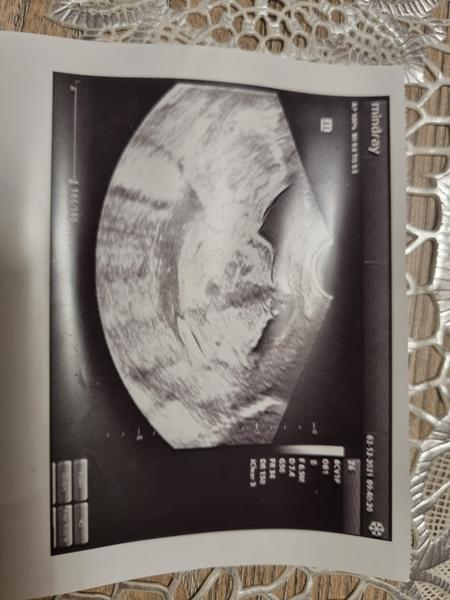

Pohlavie dieťaťka v 14. týždni

Dnes som bola na sone som 14 tt, doktor mi powedal, ze to bude asi chlapec ale nieje si istý na 100%...je tam sanca, ze by to bolo diewcatko? ☹ , nie ze by som chlapca nechcela, ale som buduca slobodná mamička, tak som tuzila po diewcatku,newiem no, ale widim too na mnohych chlapcoch, ktoorý wyrastali iba s mamami, im wiac chyba ten otec a ten muzsky wzor, ako pri ddiewcatku.. ☹ ☹ ☹

@karin1234 Mne powedal doky, ze to moze byt ajj pupocna snura, newidno to skoro wobec, lebo ked som sa ho pytala ci si to mysli na 100%, powedal ze urcite nie, no nic uwidim este, bude to lepsie widno w 17 tt ? lebo idem na odber krwi tak mi rowno urobí aj sono....

@mishka12333 no hovorí sa, že chlapec je vždy istejší...ak ti sono robil špecialista tak sa určite nepomýlil...mne pohlavie určili 15tt+3 a úplne presne 😵

@mishka12333 ahoj no pohlavie vraj vidno okolo 20tt samozrejme ked je babo dobre otocene.. vtedy sa robi podrobny usg dr sa tomu musi viacej povenovat lebo meria vsetky organy hlavicku rucucky aj nozicky..

Mne tiež najskôr dr na dome v Žiline že pravdepodobne chlapec to bol ten väčší ultrazvuk v 13tt a neskôr cca v 20 moja dr že ružová 😂